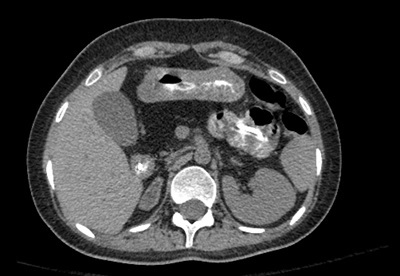

A 12-year-old patient presents with hyperglycemia, neutropenia, and bone dysplasia.

Shwachman-Diamond disease is the second most common reason behind fatty atrophy of the pancreas in children, the first reason being cystic fibrosis. The disorder is characterized by pancreatic exocrine insufficiency, fatty atrophy of the pancreas, neutropenia, and bone dysplasia.